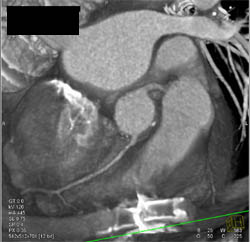

Diagnosis

Mitral Valve Replacement